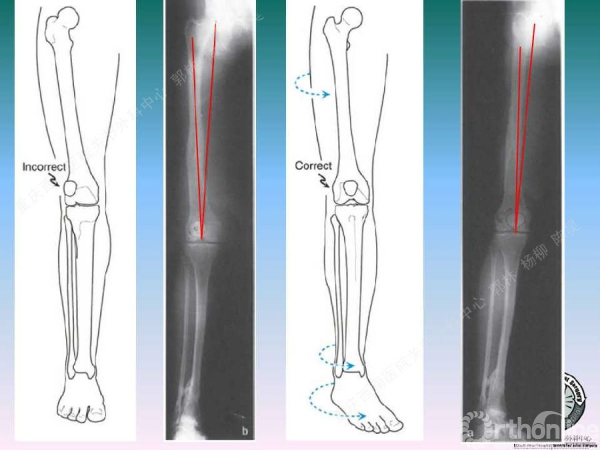

导读:文中,来自重庆西南医院的郭林教授为大家介绍了股骨冠状位关节外畸形的TKA的相关知识,并详细阐述了关节外畸形的概念、诊断、关节内滑移截骨技术等相关内容。

关节内松解矫正关节外畸形

滑移截骨纠正关节外畸形